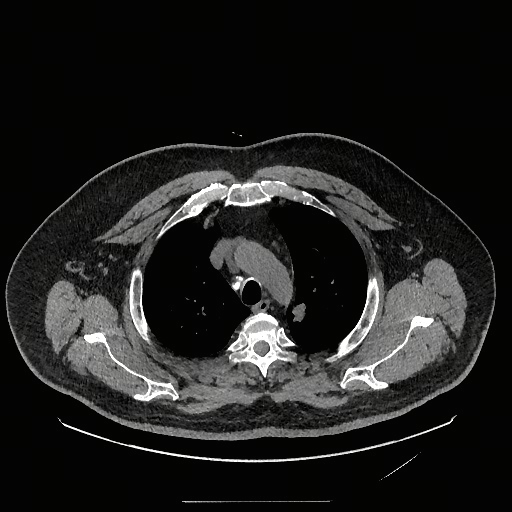

While anatomical reasoning provides the logical framework, visual limitations can hinder fine-grained detection. To address this, we integrated Think with Image [67, 22] design, enabling the model to perform secondary operations—such as rotating or zooming in—to facilitate a deeper understanding of visual information. This capability holds tremendous potential in medical imaging; for instance, zooming in on affected regions allows the model to perform granular inspection. Through exploration of tools in the multimodal domain, we identified Zoom in and Rotate as the most valuable primitives: the former is primarily designed for identifying subtle lesions in affected regions, while the latter assists with maintaining spatial orientation during the interpretation of complex medical images.

The training dataset is built mainly from radiology imaging data (e.g., X-rays, CT scans, MRI) and public de-identified radiology datasets, which include pathological/normal cases, metadata and expert annotations. Given the varying diagnostic complexity and tool utility of raw radiology data, a two-stage filtering pipeline is adopted to create an effective RL training set: